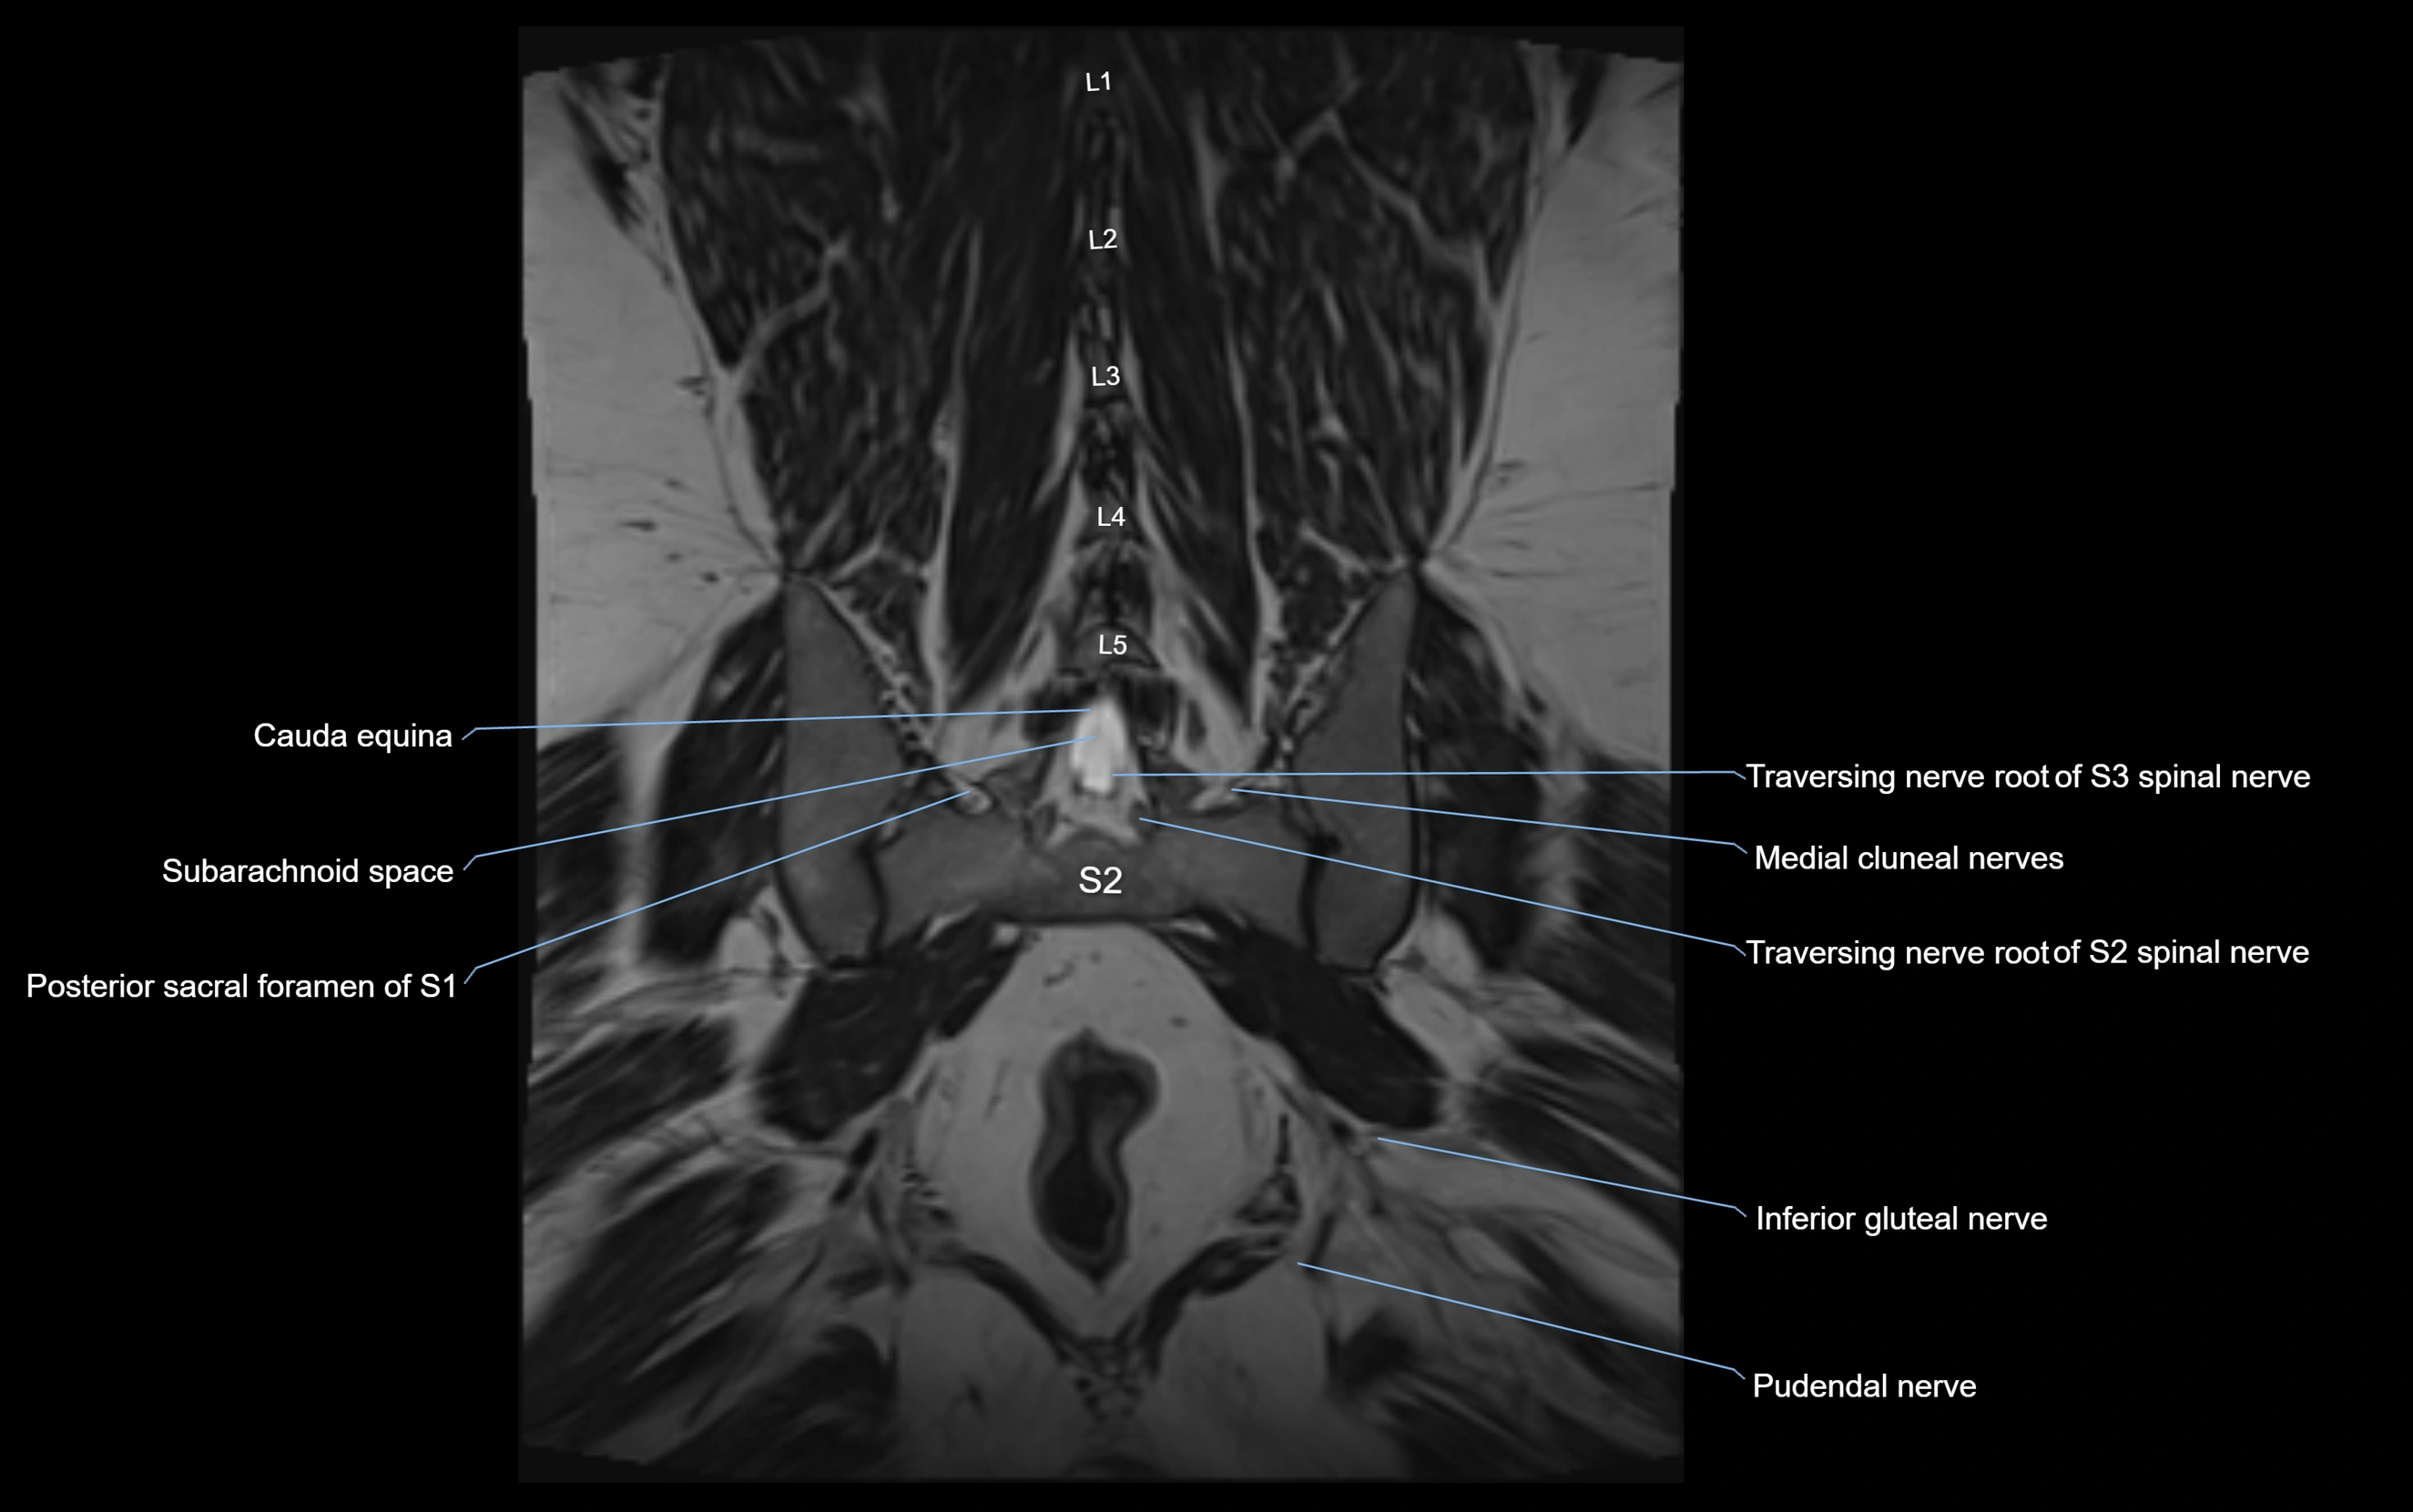

MRI image

image